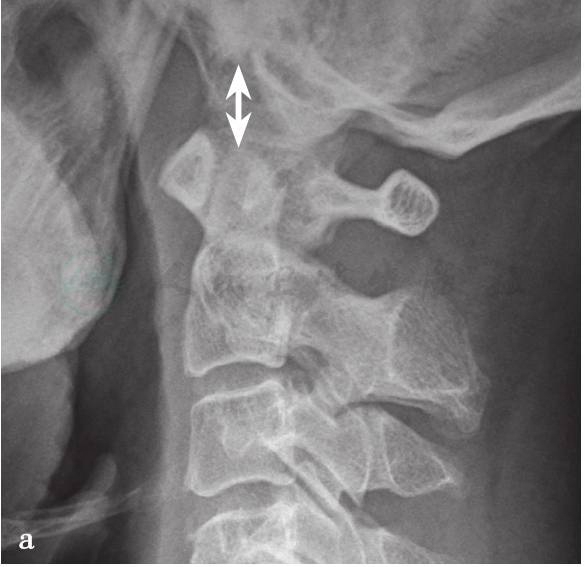

(1)齿枕间距:

在侧位X线片上测量齿突尖到枕骨大孔前缘中点的距离,其在中立位时处于一直线上,成人正常的间距为4~5mm,屈伸活动最大位移<10mm,超过10mm则视为寰枕关节不稳(图4a)。

图4

a.寰枕关节脱位X线测量方法(BDT法);b.寰枕关节脱位X线测量方法(Power法);c.寰枕关节脱位X线测量方法(Dublin法);d.寰枕关节脱位X线测量方法(Kaufman法);e.寰枕关节脱位X线测量方法(X线法);f.寰枕关节脱位X线测量方法(BAI-BDI法)